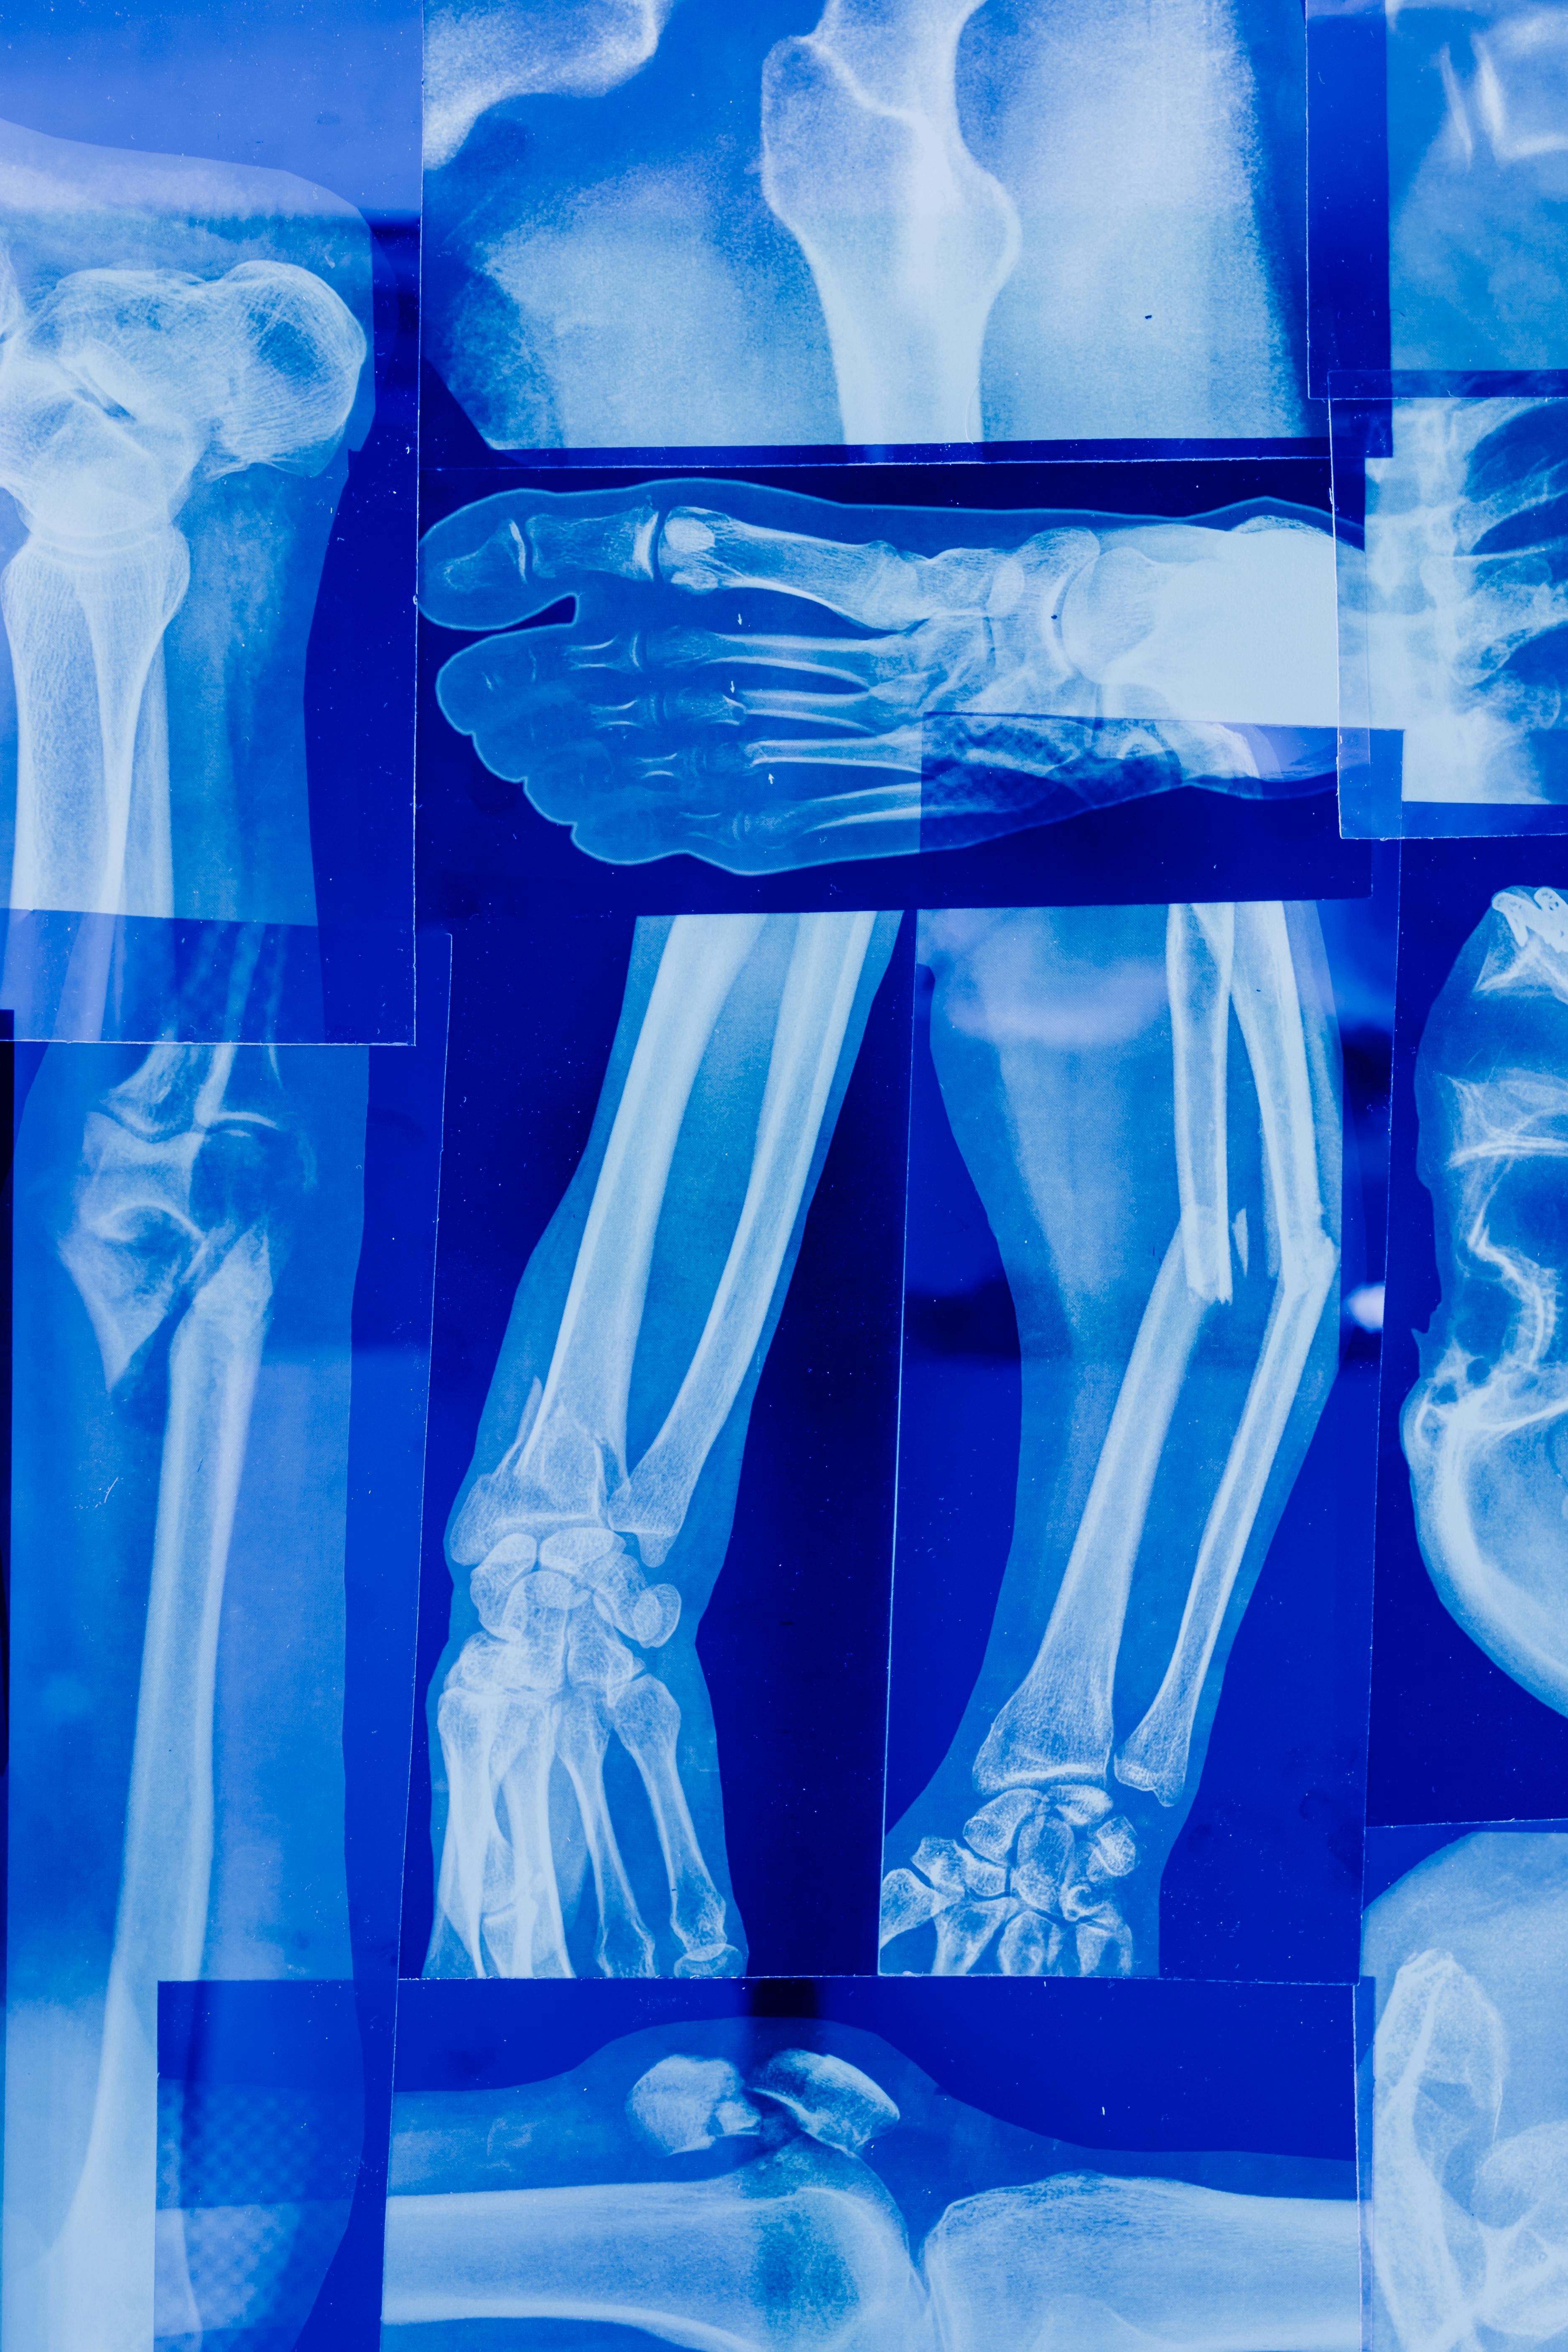

골다공증은 낮은 뼈 질량과 뼈조직의 미세구조적 악화를 특징으로 하는 전신 골격 질환으로, 뼈의 취약성과 골절에 대한 취약성이 증가합니다. 이는 전 세계적으로 수백만 명, 특히 폐경 후 여성과 노인에게 영향을 미칩니다. 골다공증은 그 조용한 성격에도 불구하고 개인과 의료 시스템에 상당한 부담을 줍니다. 그러나 증상을 이해하고 사전 예방 방법을 구현하면 영향을 완화할 수 있습니다. 이 종합 안내서에서 우리는 과학적 증거를 바탕으로 골다공증의 복잡성을 탐구하고 예방을 위한 실용적인 전략을 설명합니다..

골다공증의 결과는 골절을 넘어 확장됩니다. 척추 골절은 키 감소, 후만증, 만성 요통으로 나타나 이동성과 삶의 질을 저하시킵니다. 특히 노년층에서 널리 발생하는 고관절 골절은 상당한 이환율, 사망률 및 사회경제적 비용을 수반합니다. 더욱이 골다공증성 골절은 후속 골절의 위험을 증가시켜 장애와 의료 부담의 악순환을 영속시킵니다.